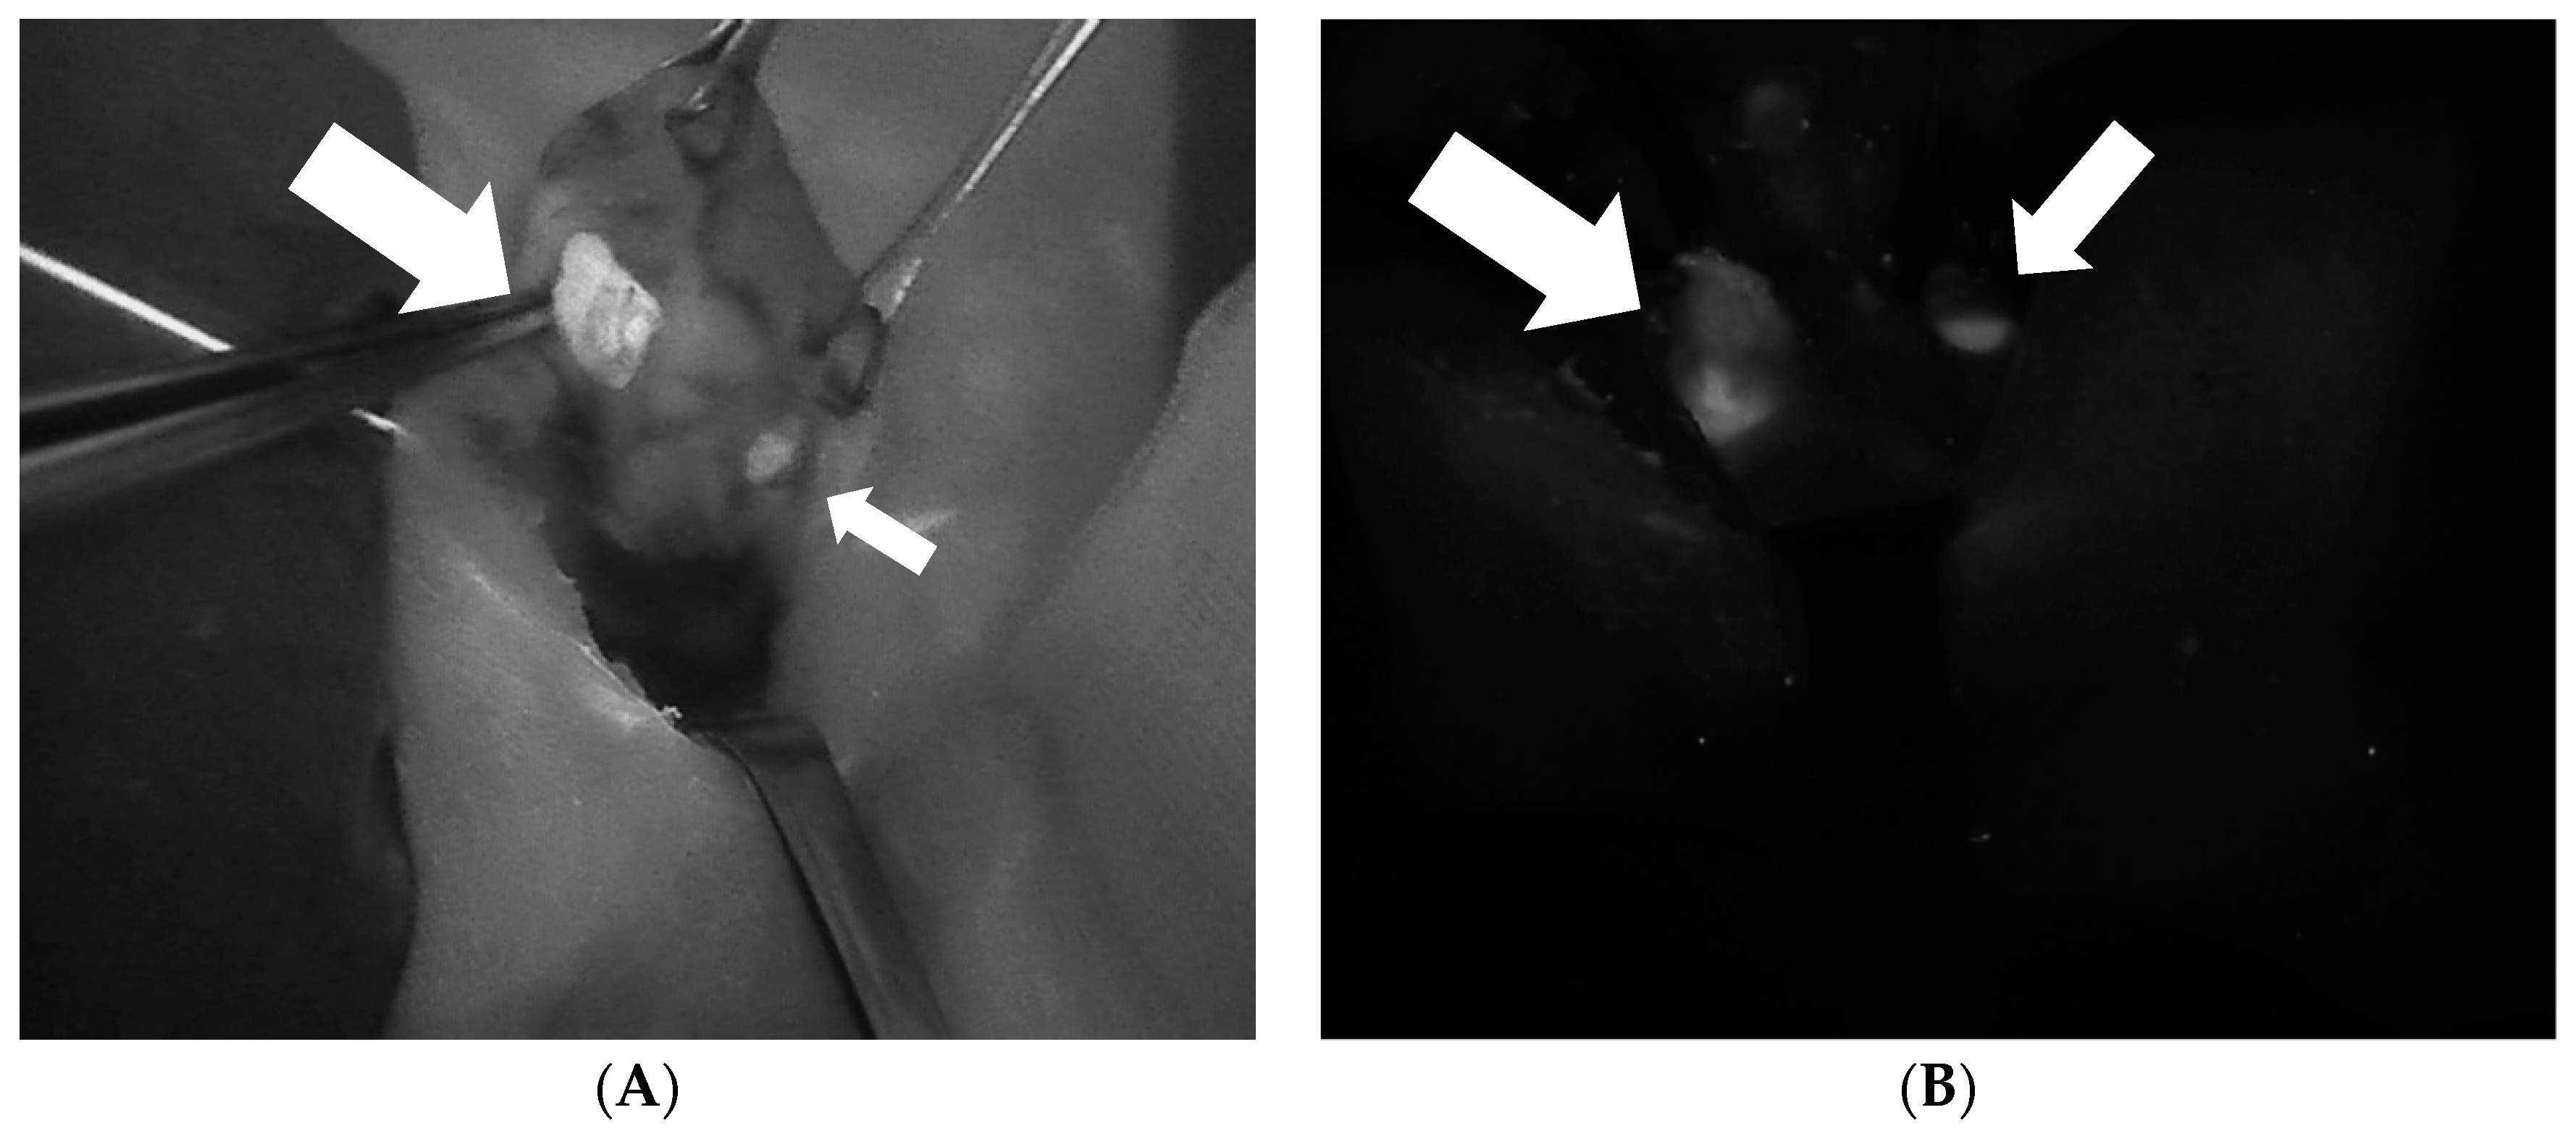

- Paras, C.; Keller, M.; White, L.; Phay, J.; Mahadevan-Jansen, A. Near-infrared autofluorescence for the detection of parathyroid glands. J. Biomed. Opt. 2011, 16, 067012. [Google Scholar] [CrossRef] [PubMed]

- McWade, M.A.; Paras, C.; White, L.M.; Phay, J.E.; Mahadevan-Jansen, A.; Broome, J.T. A novel optical approach to intraoperative detection of parathyroid glands. Surgery 2013, 154, 1371–1377. [Google Scholar] [CrossRef]

- McWade, M.A.; Paras, C.; White, L.M.; Phay, J.E.; Solórzano, C.C.; Broome, J.T.; Mahadevan-Jansen, A. Label-free intraoperative parathyroid localization with near-infrared autofluorescence imaging. J. Clin. Endocrinol. Metab. 2014, 99, 4574–4580. [Google Scholar] [CrossRef]

- Ladurner, R.; Sommerey, S.; Arabi, N.A.; Hallfeldt, K.K.J.J.; Stepp, H.; Gallwas, J.K.S.S. Intraoperative near-infrared autofluorescence imaging of parathyroid glands. Surg. Endosc. 2017, 31, 3140–3145. [Google Scholar] [CrossRef]

- Abbaci, M.; De Leeuw, F.; Breuskin, I.; Casiraghi, O.; Lakhdar, A.B.; Ghanem, W.; Laplace-Builhé, C.; Hartl, D. Parathyroid gland management using optical technologies during thyroidectomy or parathyroidectomy: A systematic review. Oral Oncol. 2018, 87, 186–196. [Google Scholar] [CrossRef]

- De Leeuw, F.; Breuskin, I.; Abbaci, M.; Casiraghi, O.; Mirghani, H.; Ben Lakhdar, A.; Laplace-Builhé, C.; Hartl, D. Intraoperative Near-infrared Imaging for Parathyroid Gland Identification by Auto-fluorescence: A Feasibility Study. World J. Surg. 2016, 40, 2131–2138. [Google Scholar] [CrossRef]

- Falco, J.; Dip, F.; Quadri, P.; de la Fuente, M.; Rosenthal, R. Cutting Edge in Thyroid Surgery: Autofluorescence of Parathyroid Glands. J. Am. Coll. Surg. 2016, 223, 374–380. [Google Scholar] [CrossRef] [PubMed]